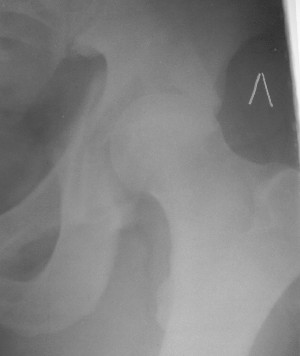

Считаю, что в представленном Вами случае целесообразно подумать о первичном протезировании. Привожу пример более легкого повреждения, где потерял время надеясь спасти сустав.

Больной 18 мая 2003 года в автоаварии получил перелом левой вертлужной впадины, вывих бедра. Госпитализирован в один из стационаров области.Вывих вправлен. В последствии бедро вывихивалось еще дважды. На консультацию был представлен снимок от 19.05.03г., больной переведен к нам 3.06.03г. Снимок при поступлении - перелом впадины, задне-верхний вывих бедра. 05.06.2003 г. выполнено открытое вправление вывиха левого бедра и остеосинтез стенки вертлужной впадины двумя винтами. Послеоперационный период без осложнений. Объем движений в левом тазобедренном суставе восстановился полностью. Выписан на амбулаторное лечение в удовлетворительном состоянии с рекомендациями 3 месяца ходить на костылях без нагрузки на оперированную конечность. На контрольных рентгенограммах левого тазобедренного сустава 13.10.2003 г. - признаки консолидации перелома; плотность, форма головки и состояние суставных поверхностей удовлетворительные. Разрешена дозированная осевая нагрузка, на конечность с использованием дополнительной опоры. 19.12.2003 г. больной обратился с жалобами на боли в левом тазобедренном суставе. На рентгенограммах левого тазобедренного сустава 19.12.2003 г., 20.02.04г. - асептичекий некроз головки бедра. 5.04.04г. - эндопротез. Сейчас ходит без трости, не хромает. Особенность эндопротезирования - при удалении винтов прослежена линия перелома заднего края впадины и предложено установить чашку несколько меньшего диаметра, чтобы она была покрыта несломанной частью.